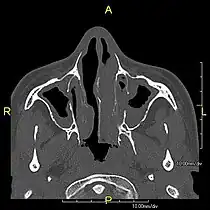

Axial CT image showing dextrocardia with the IVC and morphologic right ventricle on the left and the left ventricle on the right